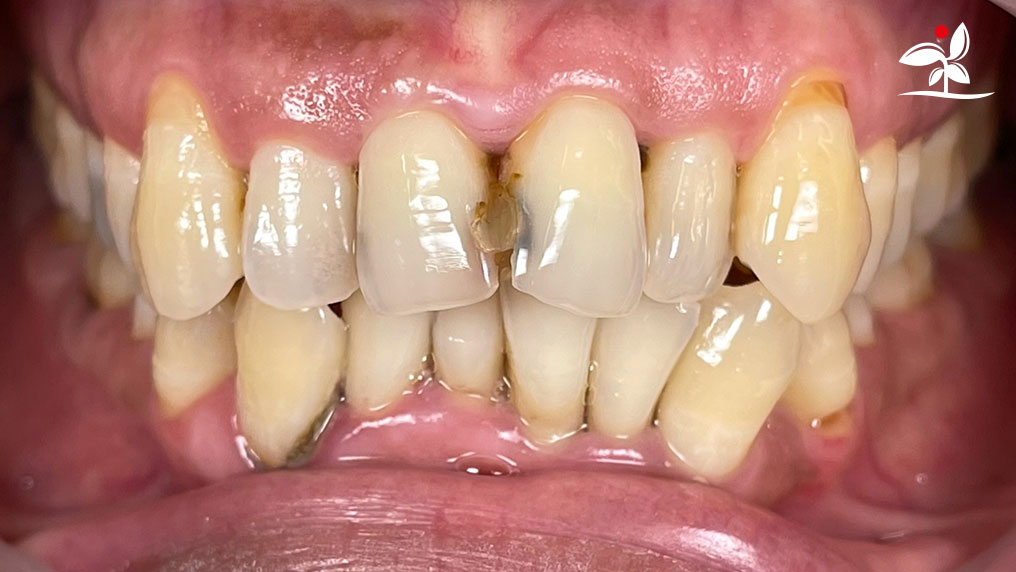

Restoration of Class IV Lesions using Naturomimetic Layering Technique (NLT) and Bioactive Restorative Materials

With the growing awareness about the health, function and aesthetic benefits of preserving natural tooth structure, patients are now globally demanding for aesthetic dentistry with minimally invasive procedures that has a low biological cost. This public demand has encouraged logical clinicians to adopt to the minimally invasive cosmetic dentistry (MiCD) concept and its treatment protocol [1] in their practice. The author has been using MiCD concept and its treatment protocols since 2017, which

include the methods of treatment that are simple, fast, predictable and healthy. In aesthetic restoration, the tooth color restorative materials placement technique is one of the most challenging, confusing and frustrating areas to learn owing to the multiple techniques that have been proposed by many clinicians and replicating such techniques in practice is not always as easy as they are marketed in dentistry. Natural teeth are complex in structure and hard to simulate due distribution of colors through enamel and dentin [2]. Aesthetic restoration strategies should follow proper understanding of defects, right selection of restorative materials along with their proper application, finishing, texturing and polishing [2].